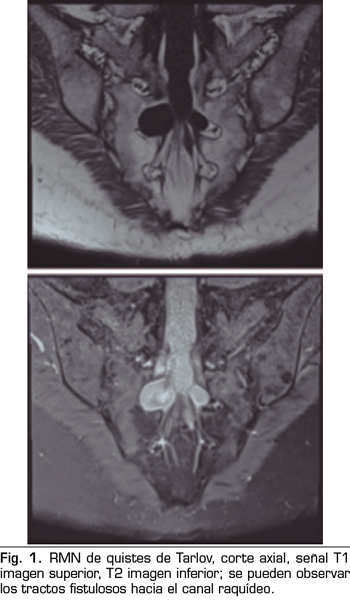

Los “quistes perineurales” o “Quistes de Tarlov” son alteraciones en la duramadre de las raíces nerviosas, que se producen más frecuentemente en la zona sacra. El diagnóstico suele ser casual mediante RMN; la incidencia es variable, debido a que el hallazgo es incidental. Habitualmente son asintomáticos, pero pueden producir radiculopatía, dolor perineal o vejiga neurógena, entre otros.

Figura 2